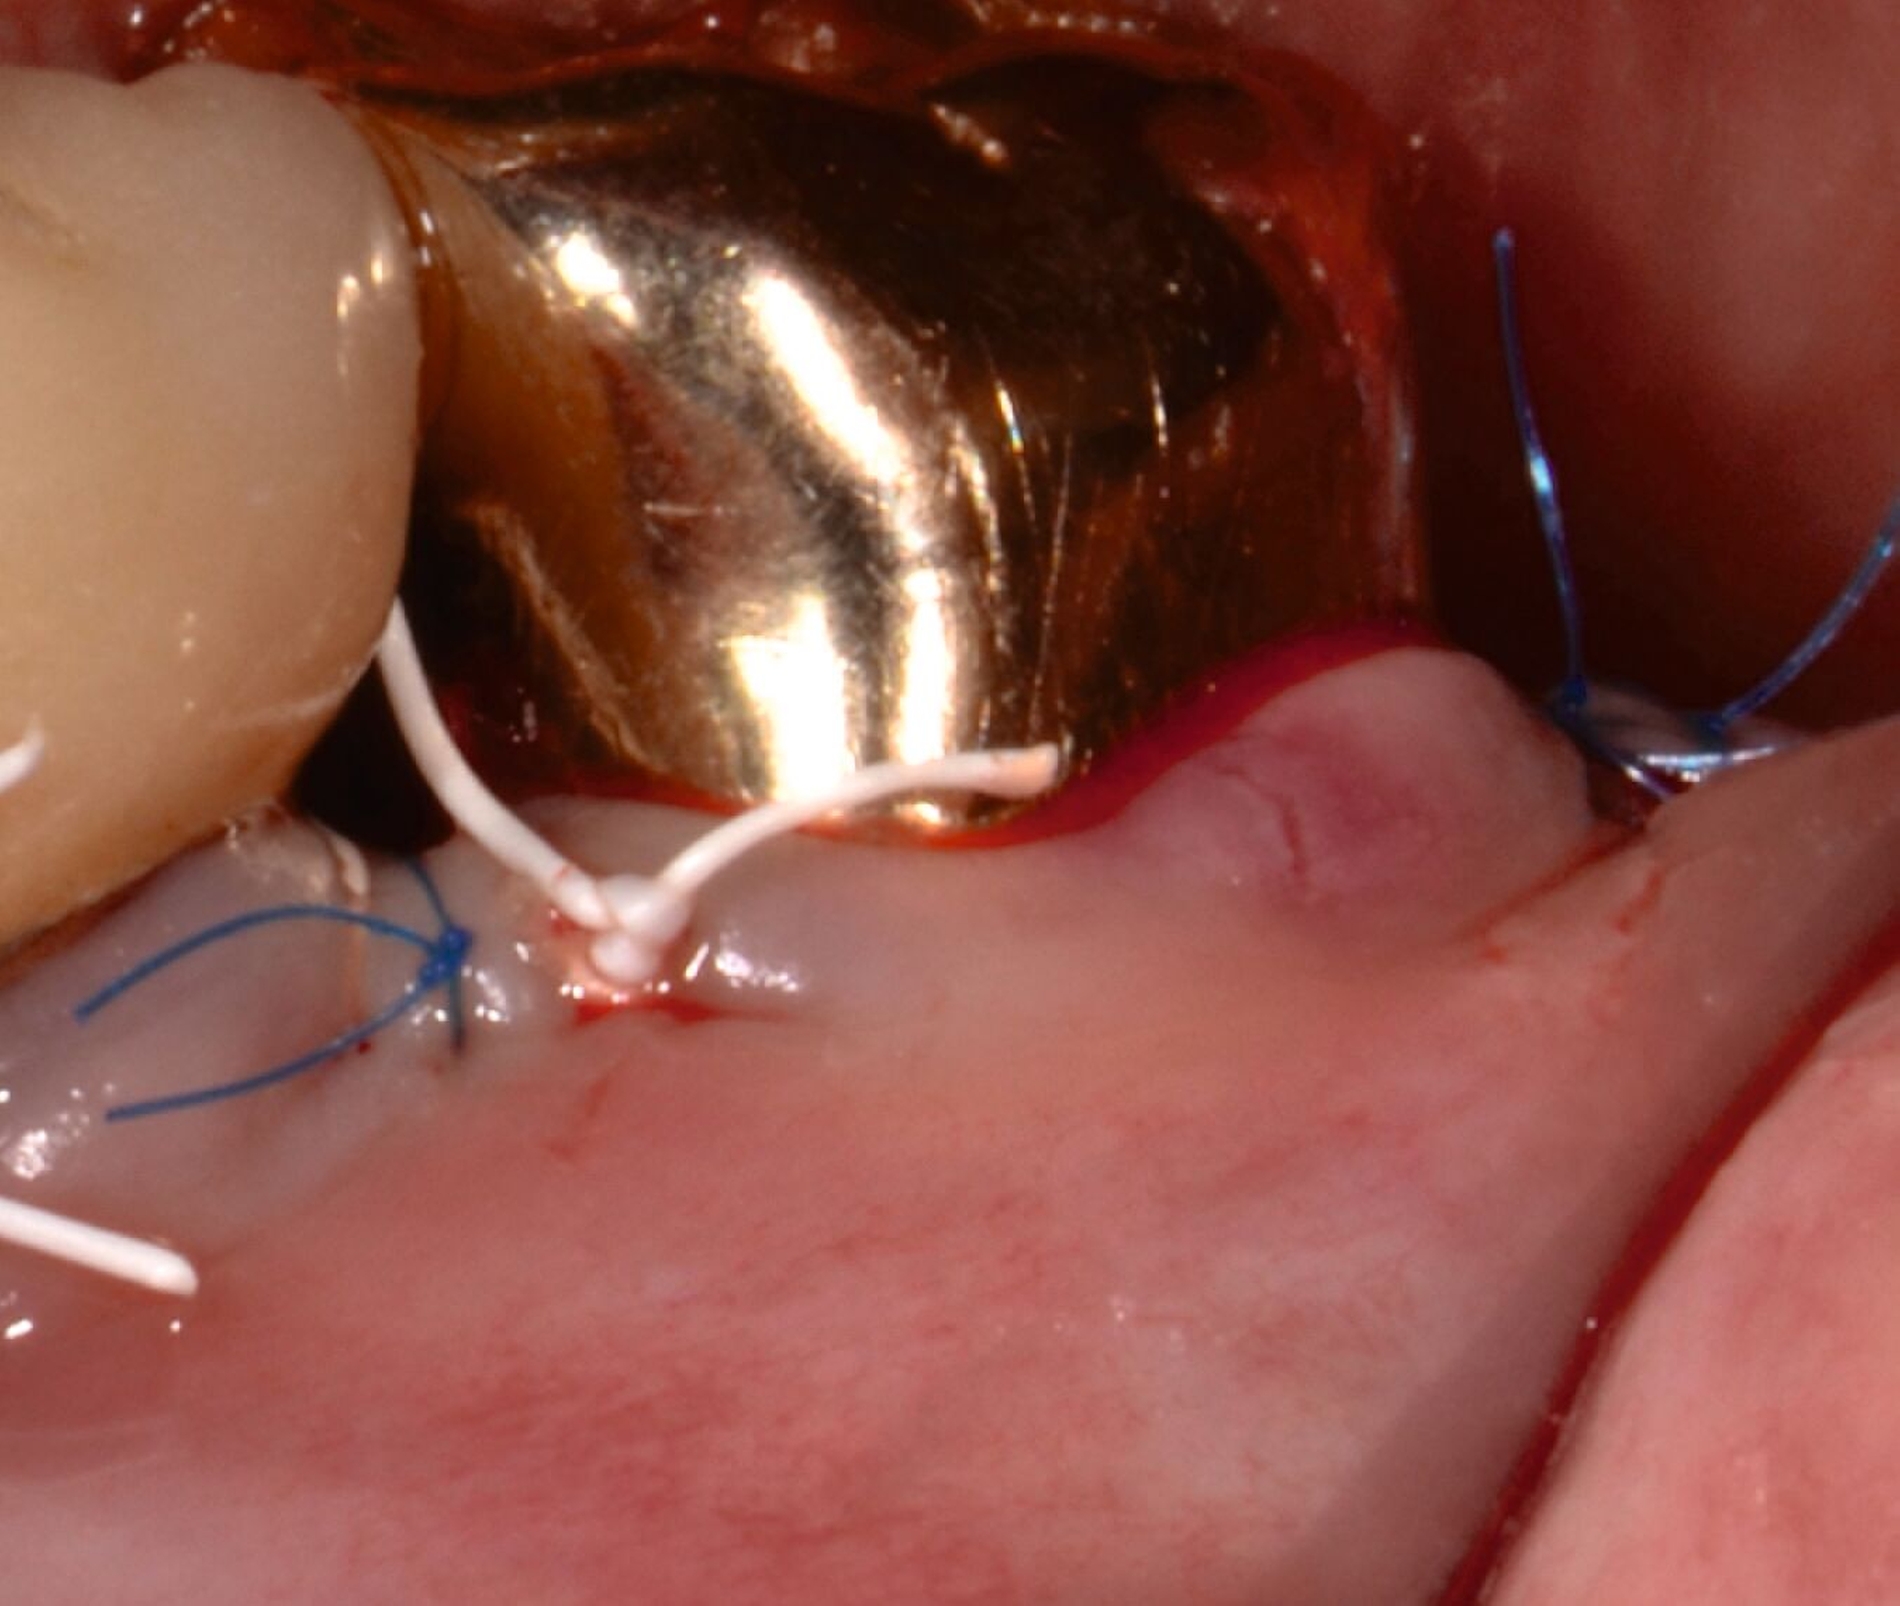

Alternativ kann eine GTR-Barrieremembran mit oder ohne zusätzlichen Defektfüller appliziert werden. Die Barrieremembran wird mit einer resorbierbaren Umschlingungsnaht befestigt, um den Furkationseingang abzudecken und die Wund- und Koagulumstabilisierung zu fördern. Um eine vollständige Abdeckung der Barriere zu ermöglichen, kann das Periost durchtrennt werden, um den Lappen leicht koronal zu verschieben. Der Lappen wird mit einer Umschlingungsnaht und Einzelknopfnähten über den vertikalen Entlastungsinzisionen oder mit interdentalen Nähten im Fall eines lateral extendierten Lappens in einer koronalen Position gesichert. Der Patient wird angewiesen, für einen Zeitraum von bis zu vier Wochen auf die mechanische Plaqueentfernung im Operationsgebiet zu verzichten. Während dieser Zeit werden Chlorhexidin-Spülungen oder -Gel verwendet. Der Patient kehrt zur Kontrolle der Wundheilung nach ein und zwei Wochen zurück, wenn die Nähte entfernt werden. Die Interdentalhygiene und die mechanische Plaqueentfernung werden nach vier Wochen wieder aufgenommen. Zudem wird ein individuelles Recallprogramm zur unterstützenden Parodontitistherapie (UPT) festgelegt.